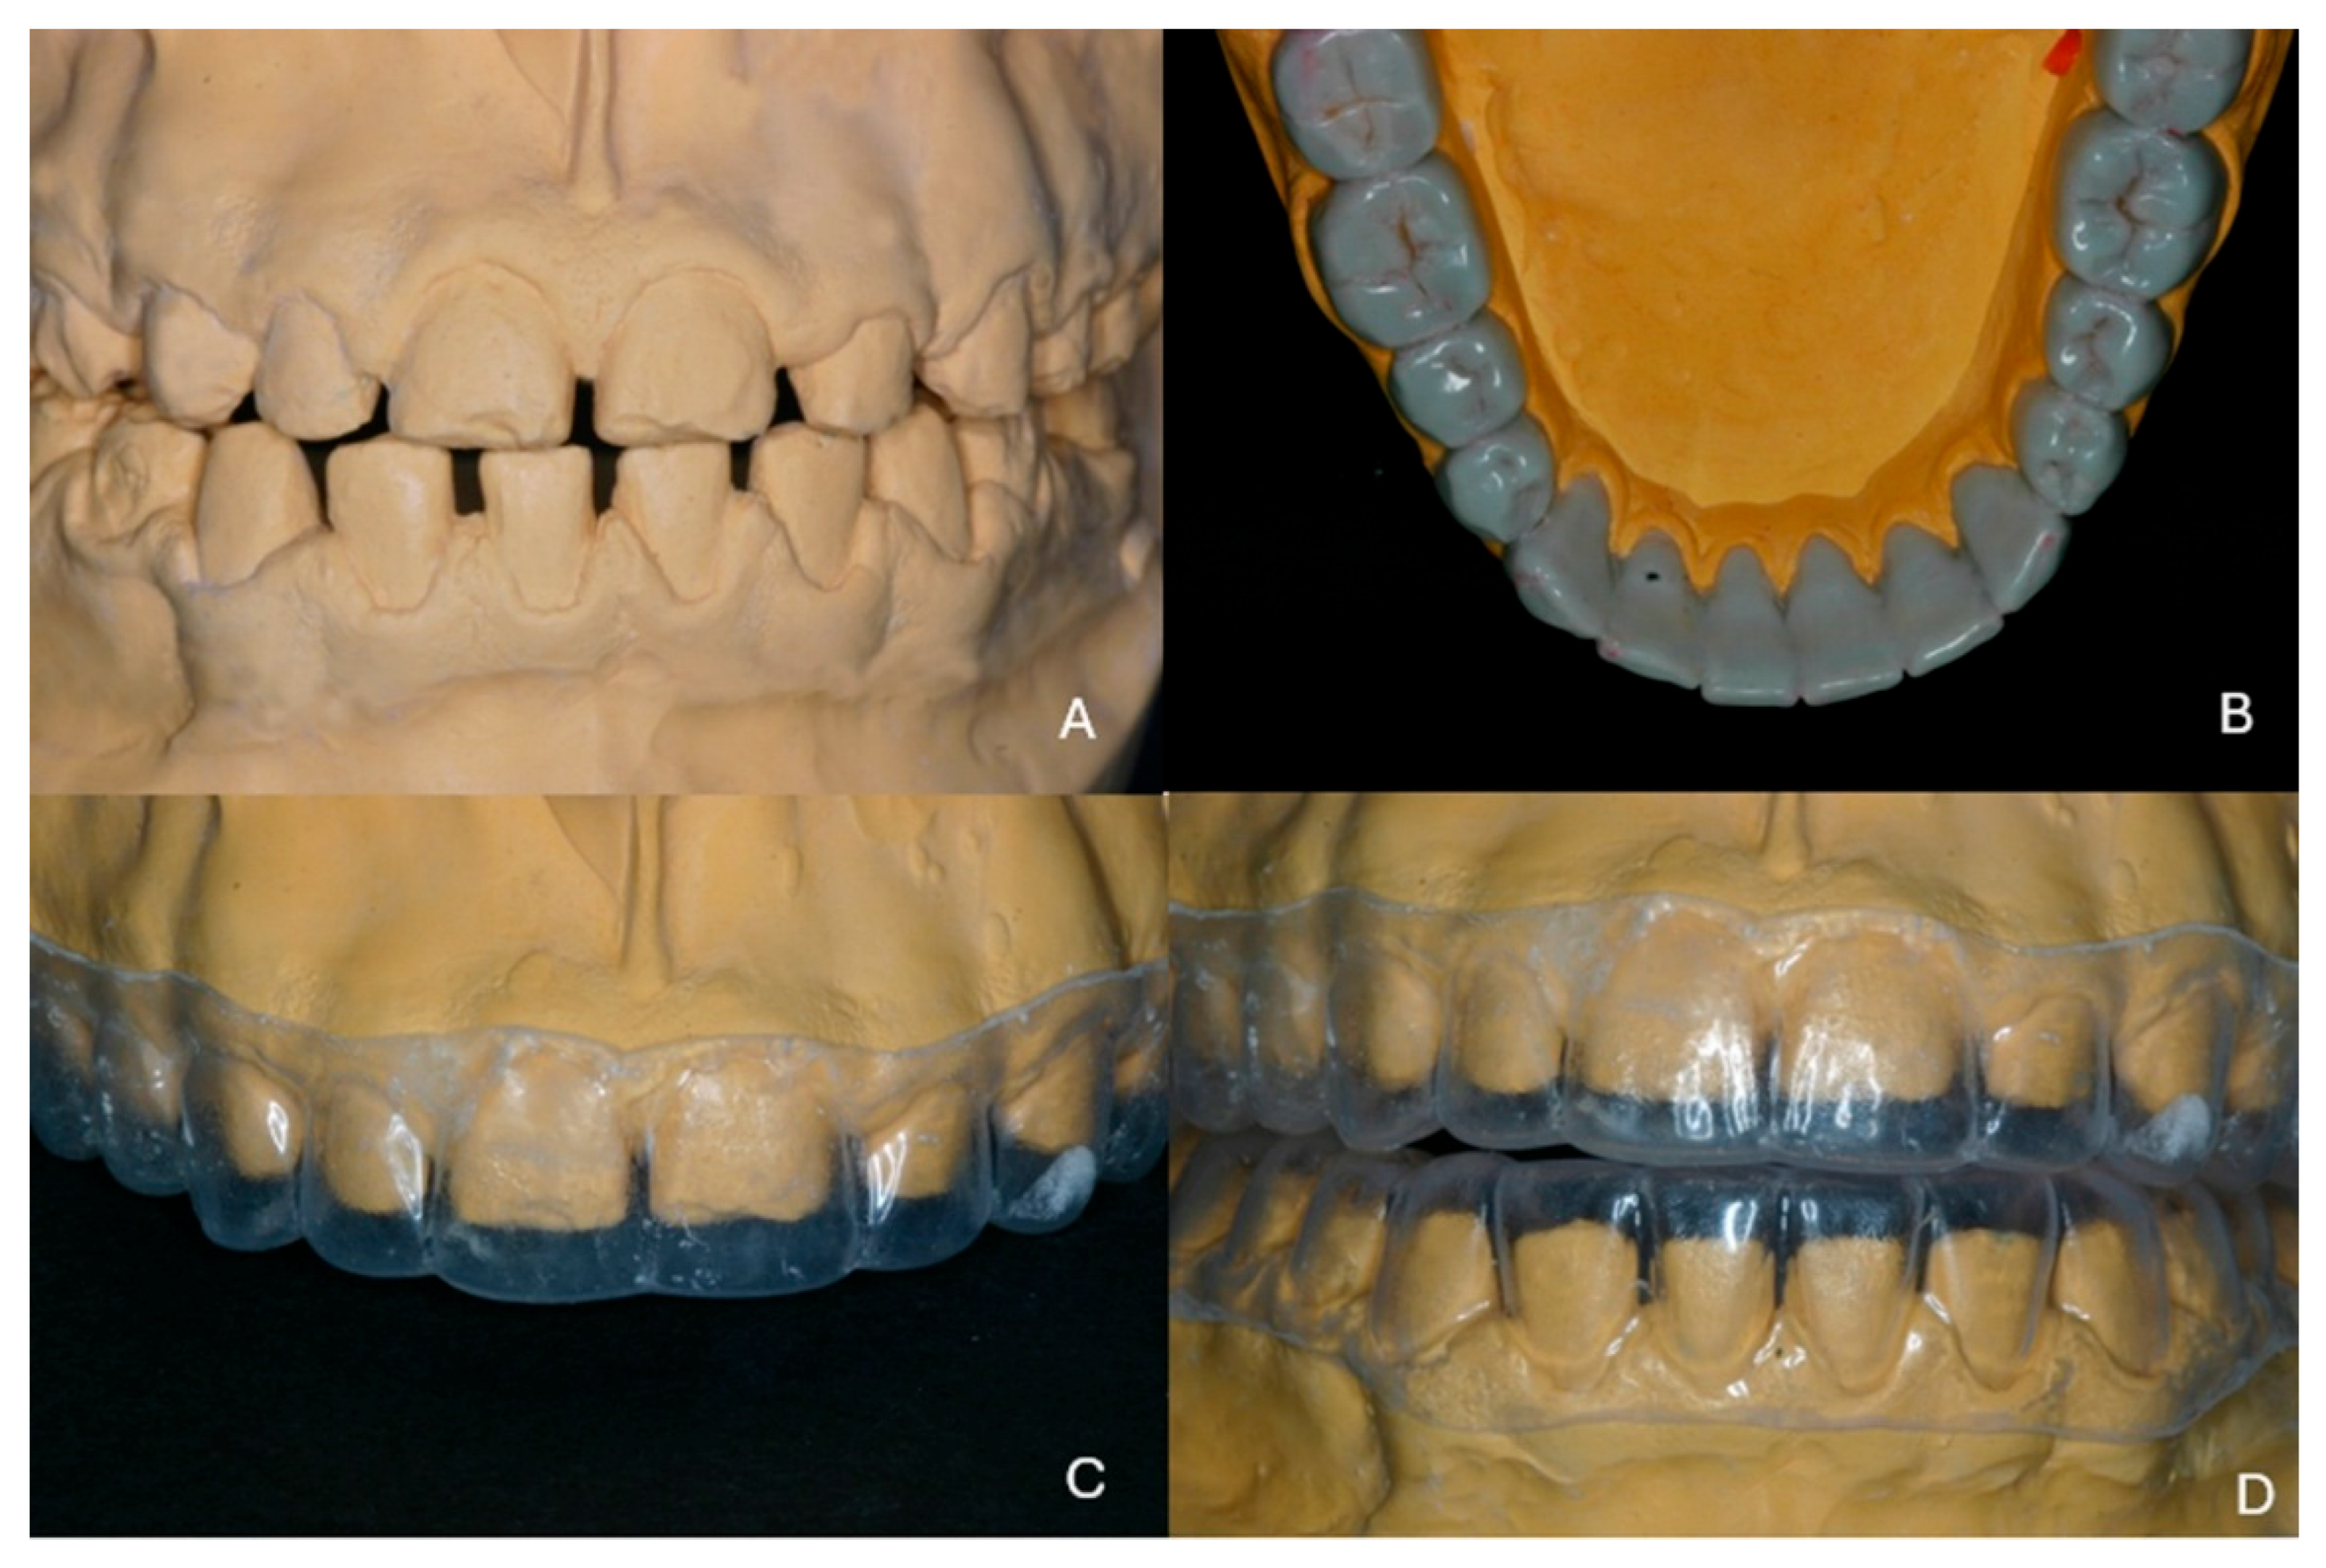

Full Mouth Rehabilitation with All-Ceramic Restorations in a Patient with Amelogenesis Imperfecta: A Case Report with 10-Year Follow-Up

2. Case Presentation